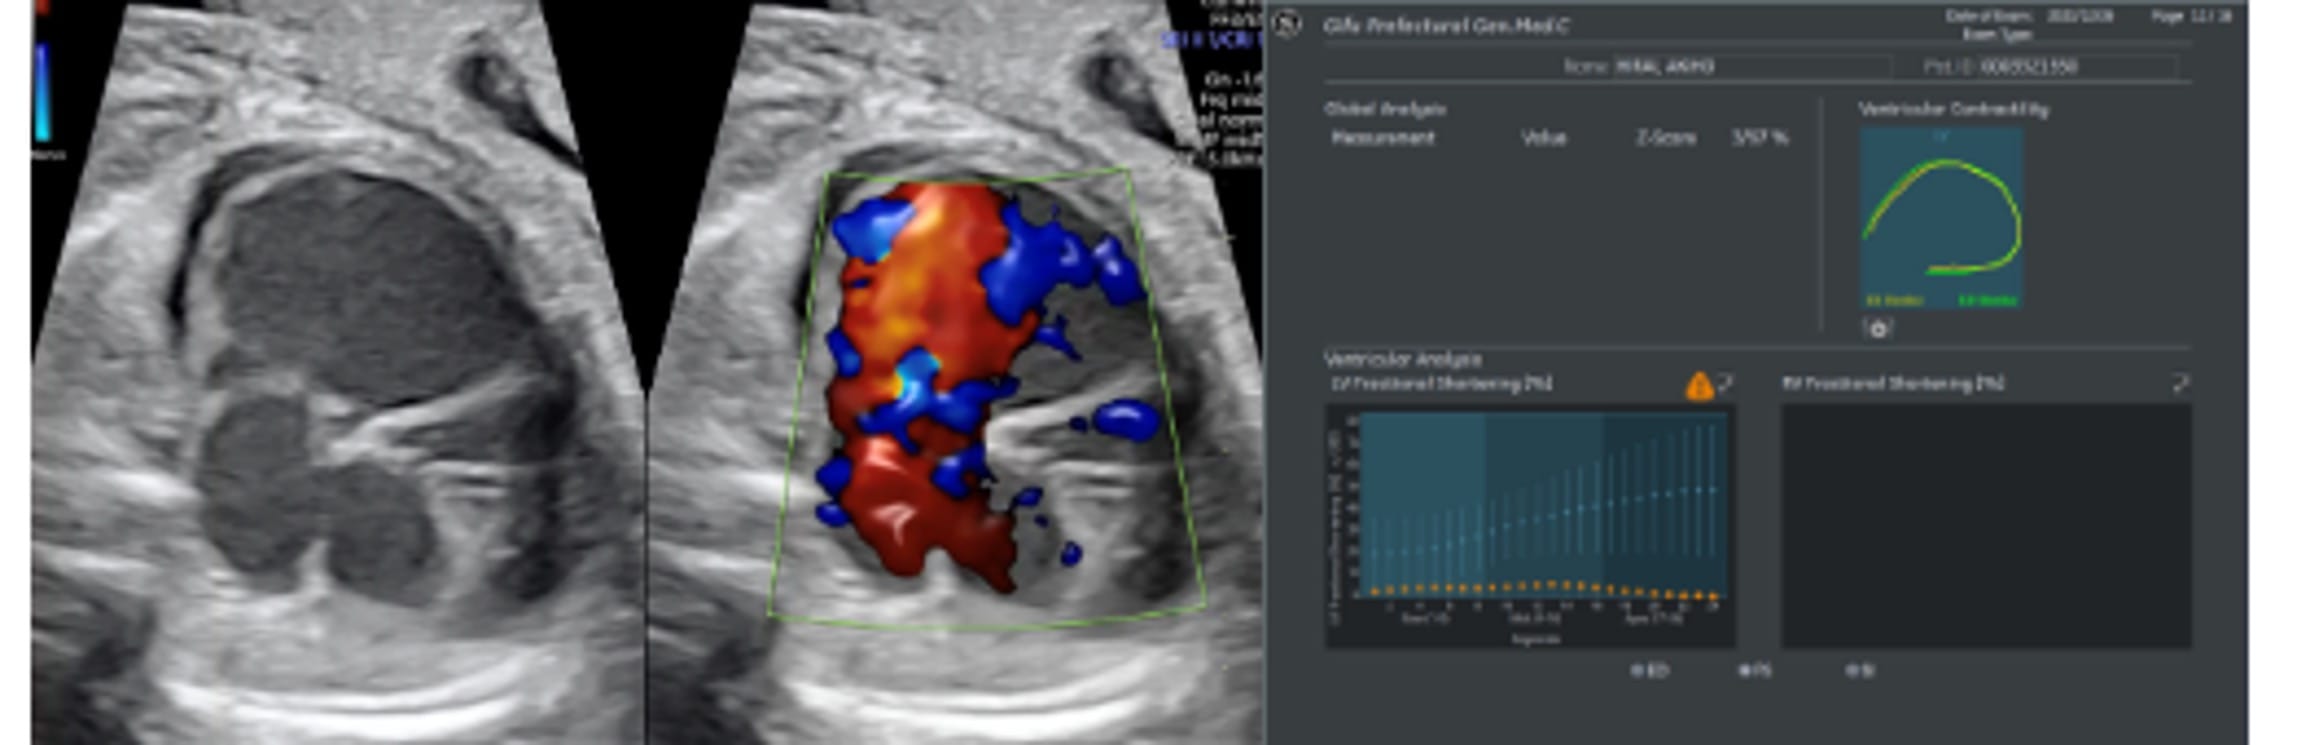

Fetal HQ

Fetal HQ®はSpeckle-Tracking法を用いて胎児心室壁の運動を解析する方法です。Speckle-Tracking法とは心筋の断層エコー画像上の小斑点(speckle)を追跡し心筋局所の機能を解析する方法で、成人の心臓超音波検査でも用いられています。一回数秒の動画の保存で複数の心機能が同時に評価できる新しい検査法です。

Global strain

(収縮末期心室内周長−拡張末期心室内周長)/拡張末期心室内周長×100で表され、心筋全体のストレイン(伸び縮み)を数値化することで心筋の三次元的な動きを評価する。

Fetal HQの臨床における活用はまだ限定的です。当院では先天性心疾患の胎児や、双胎間輸血症候群・胎児胸水・胎児貧血といった胎児治療が必要な胎児の心機能を評価するために、従来用いられている心機能の評価項目に加え、Fetal HQを用いて心エコー検査を行っています。データを積み上げ、Fetal HQの活用の幅を広げていきます。